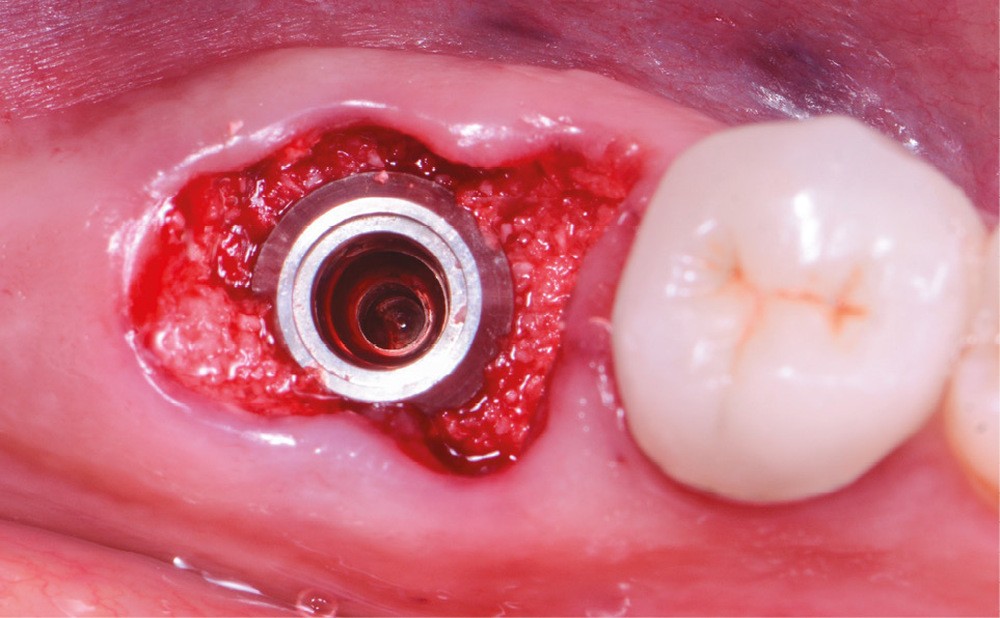

6. Vue occlusale du site après l’implantation immédiate et le comblement alvéolaire par matériau xénogénique.

Le pilier SSA, ou vis de fermeture d’alvéole (« sealing socket abutment »), est un pilier de cicatrisation anatomique et personnalisé assurant l’herméticité entre le site chirurgical et la cavité orale dans le cadre des thérapeutiques d’extraction implantation immédiate. Nous illustrons ce concept à travers un cas clinique.

Au vu du faible niveau de preuve scientifique et du rapport bénéfice/risque pour le patient concernant la réhabilitation provisoire immédiate en secteur molaire, il semble évident qu’il n’est ni nécessaire ni utile d’envisager ce type de projet prothétique le jour de l’extraction. Néanmoins, un défi majeur soulevé par l’implantation immédiate dans le secteur molaire est la capacité du praticien à fermer le site alvéolaire post-extractionnel de manière hermétique.